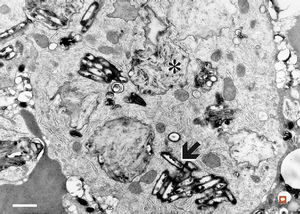

F,41y. | Whipple disease - duodenum